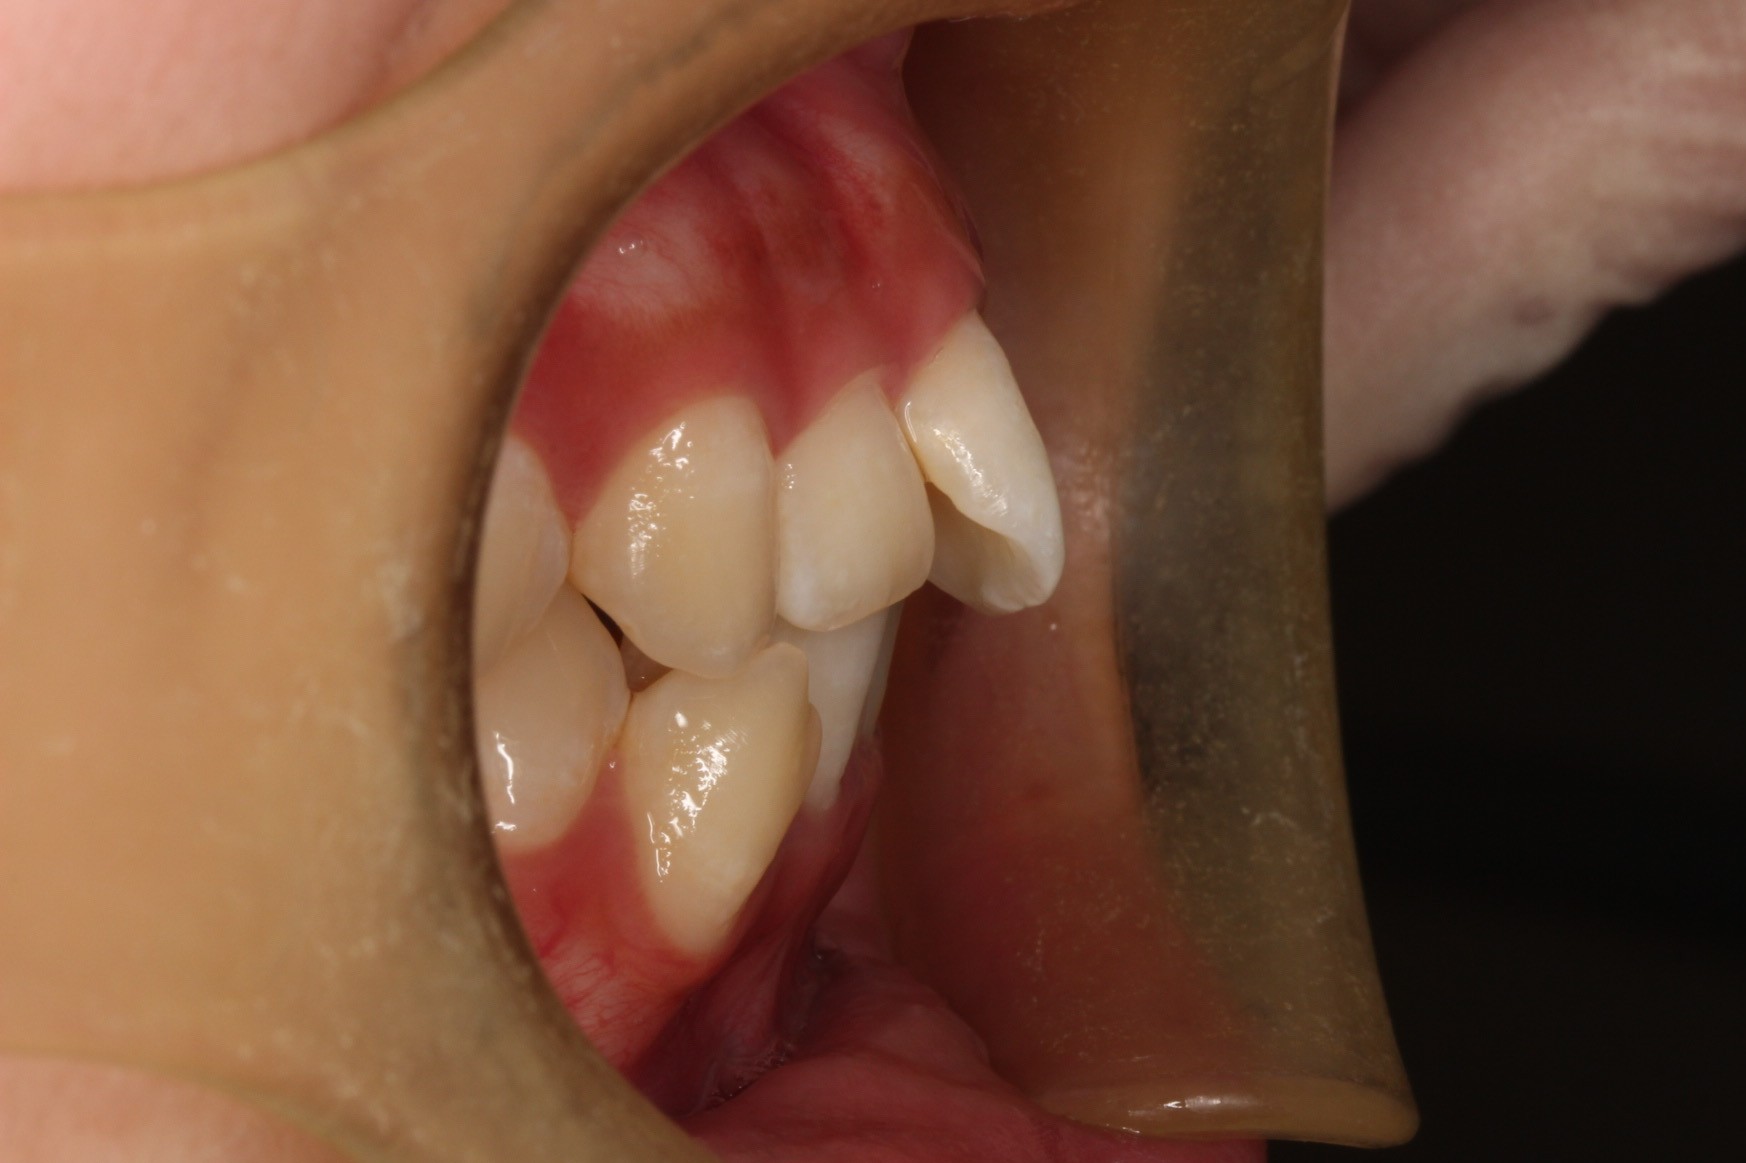

矯正術前:右側

矯正術後:右側

今回ご紹介する患者様は、上下のがたつきを気にされており、矯正検査後叢生Ⅰ級と診断いたしました。

矯正前に、上下小臼歯4本を抜歯いたしました。また、ワイヤー矯正後に、インビザラインで仕上げ矯正を行いました。

| 治療内容 | 患者様は、上下のがたつきを気にされており、矯正検査後叢生Ⅰ級と診断いたしました。矯正前に、上下小臼歯4本を抜歯いたしました。また、ワイヤー矯正後に、インビザラインで仕上げ矯正を行いました。 |